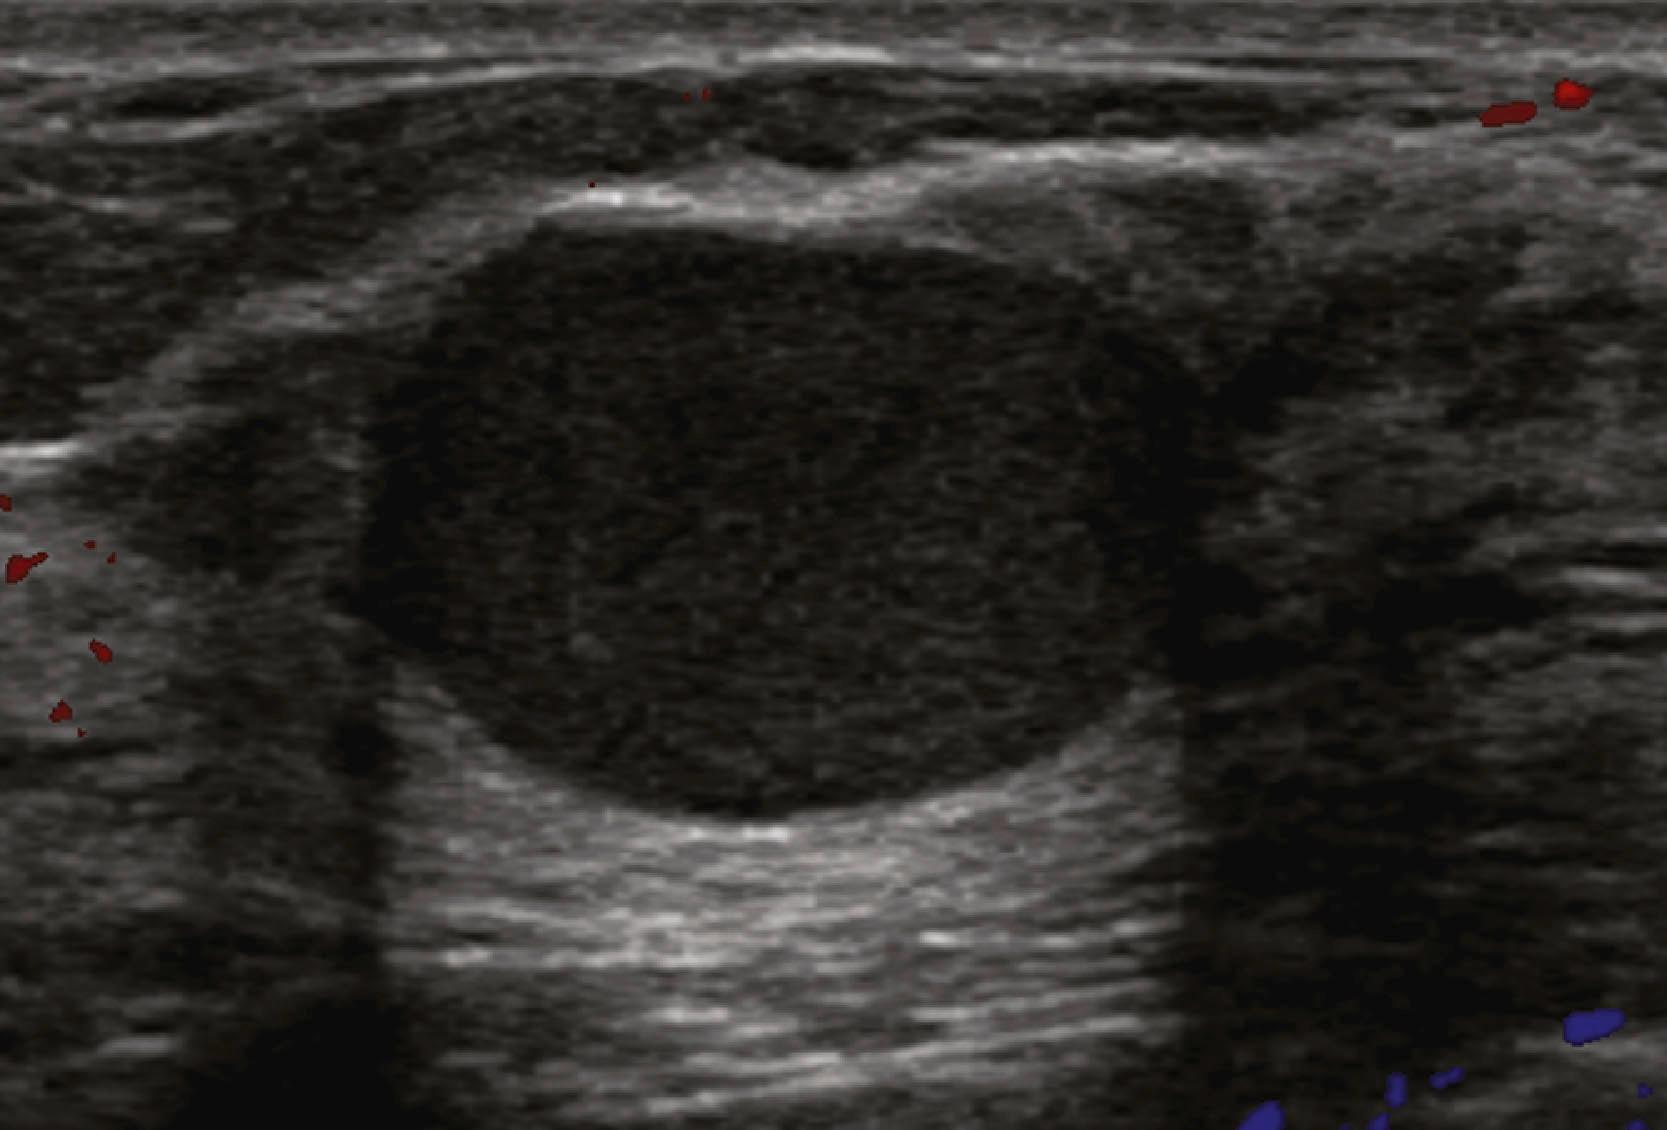

Sonographic features of simple cysts include well-defined margins, anechoic contents, and acoustic enhancement (increased sound transmission through the fluid compared with the surrounding tissue) ( Fig. 8.12 ). Simple cysts are rarely aspirated except for relief of patient symptoms, and the fluid obtained is often discarded rather than sent for cytological evaluation. However, some cysts contain internal echoes and are aspirated or undergo biopsy percutaneously to determine whether they are indeed complicated cysts or solid masses ( Fig. 8.13 ). The aspirate cytology of these complicated cysts does not always contain ductal epithelial cells, leading the pathologist to report the sample as suboptimal. A complex cyst (now referred to as a complex cystic and solid mass) is one that contains a mass or has complex internal architecture and will undergo biopsy of the noncystic portion, which may represent an intracystic papilloma or carcinoma ( Fig. 8.14 ).

Fig. 8.12, A simple cyst is anechoic (no internal echoes) because it is fluid filled and has no interfaces within, has smooth walls, and exhibits acoustic enhancement (arrows) owing to greater transmission of sound through fluid compared with adjacent tissue, where more sound is absorbed or reflected owing to the multiple interfaces in solid tissue.

Fig. 8.13, A complicated cyst contains low-level internal echoes owing to complex fluid content, is sometimes termed a debris-filled cyst, and cannot be distinguished from a solid mass without aspiration of its contents.